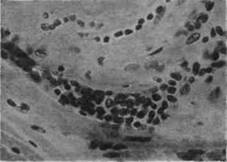

Относительно характера и частоты поражения сердца при полиомиелите были высказаны разные точки зрения. В зарубежной литературе сложилось мнение о большей частоте миокардита при полиомиелите, от 20-30% при одних и до 50% при других эпидемических вспышках. В миокарде в большинстве случаев находят умеренно выраженные интерстициальные изменения без грубой деструкции мышечных волокон (рис.1). Тяжелый паренхиматозный миокардит описан только в отдельных случаях. По данным Е.К. Жуковой (1959), только в двух из 19 случаев отмечен интерстициальный миокардит. Расхождение во взглядах на частоту миокардита при полиомиелите объясняется вернее всего неодинаковой оценкой изменений, обнаруженных в строме миокарда, которые не всегда дан" основания рассматривать их как миокардит.

Рис.13. Сердечная мышца: отек межуточной ткани, инфильтрация ее лимфоидными и гистиоидными элементами.

Следует, однако, учитывать, что штаммы вируса полиомиелита, выделенные в разные эпидемические вспышки, могут обладать неодинаковым тканевым тропизмом-свойством, присущим и другим кишечным вирусам (вирус Коксаки, тип Б и др.). Поражение нервных аппаратов сердечной мышцы, отмеченное и при полиомиелите человека (Е.К. Жукова, 1957) и при экспериментальном полиомиелите обезьян (А.Л. Юровская), делает вероятным роль неврогенного механизма в поражении миокарда. Возможно, что изменения иннервационных аппаратов сердца, поражение которых носит обратимый характер, лежат в основе часто наблюдаемых при полиомиелите нарушений сердечной деятельности. Способность к восстановлению этих нарушений установлена клиническими и электрокардиологическими наблюдениями.